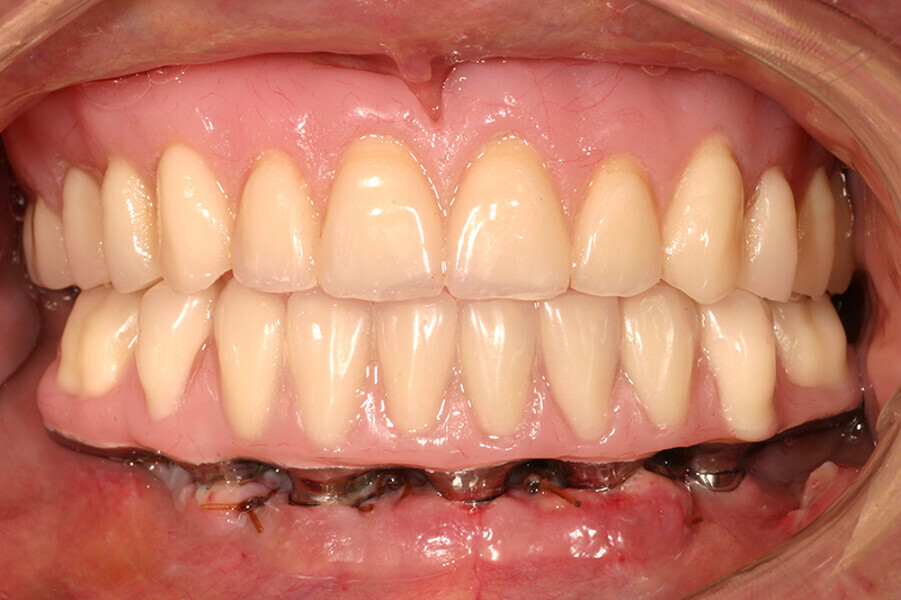

Fig. 10. Prótesis híbrida inmediata con 10 años de evolución y Rx Control a los 10 años.

Fig. 11. Prótesis híbrida inmediata con 10 años de evolución y Rx Control a los 10 años.